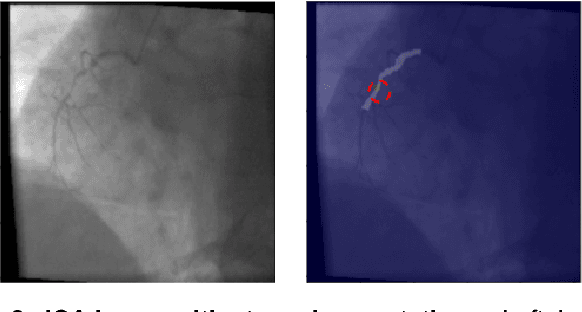

Automated Characterization of Stenosis in Invasive Coronary Angiography Images with Convolutional Neural Networks

Figure 2 for Automated Characterization of Stenosis in Invasive Coronary Angiography Images with Convolutional Neural Networks